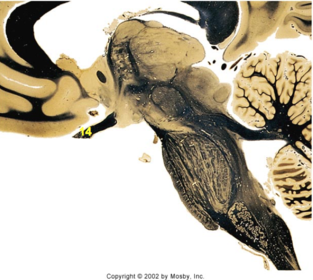

| Head of caudate | |

| Anterior commissure | |

| Thalamus | |

| Substantia nigra | |

| Optic tract | |

| Dentate nucleus | |

| Pons | |

| Longitudinal pontine fibers | |

| Uncus | |

| Superior cerebellar peduncle | |

| Red nucleus | |

| Corticospinal tract (dark) | |

| Pontine nuclei (pale) | |

| Transverse pontine fibers (dark) | |

| Inferior olive | |

| CTT | |

| Medial lemniscus | |

| Nucleus cuneatus | |

| Superior colliculus | |

| Inferior colliculus | |

| Optic nerve | |

| Cerebellum | |

| 4th ventricle | |